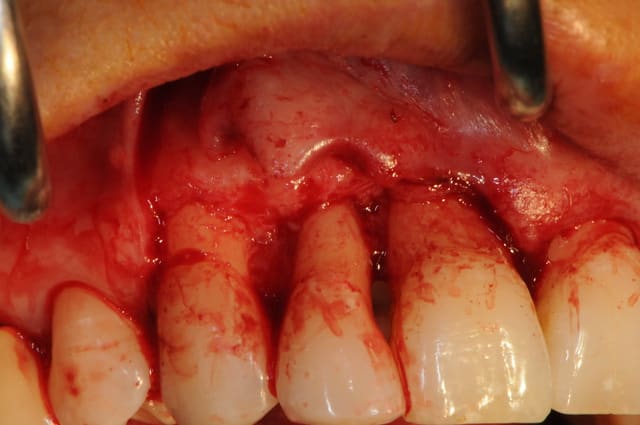

la ROG maintenant... ou "comment essayer de sauver les meubles"

Puisque tu as voulu gérer en extraction implantation ce cas délicat avec une perte osseuse pourquoi avoir fait un lambeau ?

Une technique sans lambeau (avec comblement osseux des gap sur 12 et 22 et pourquoi pas des alvéoles de 11/21) me semblait plus appropriée pour réduire la perte osseuse et gingivale ainsi qu'une fermeture des sites de 11 et 21 à l'aide d' un greffon epithélio conjonctif circulaire.

A ta place j'attendrai que les implants soient ostéo intégrés avant de tenter quoique ce soit: ROG ou greffe conjonctif enfoui ...